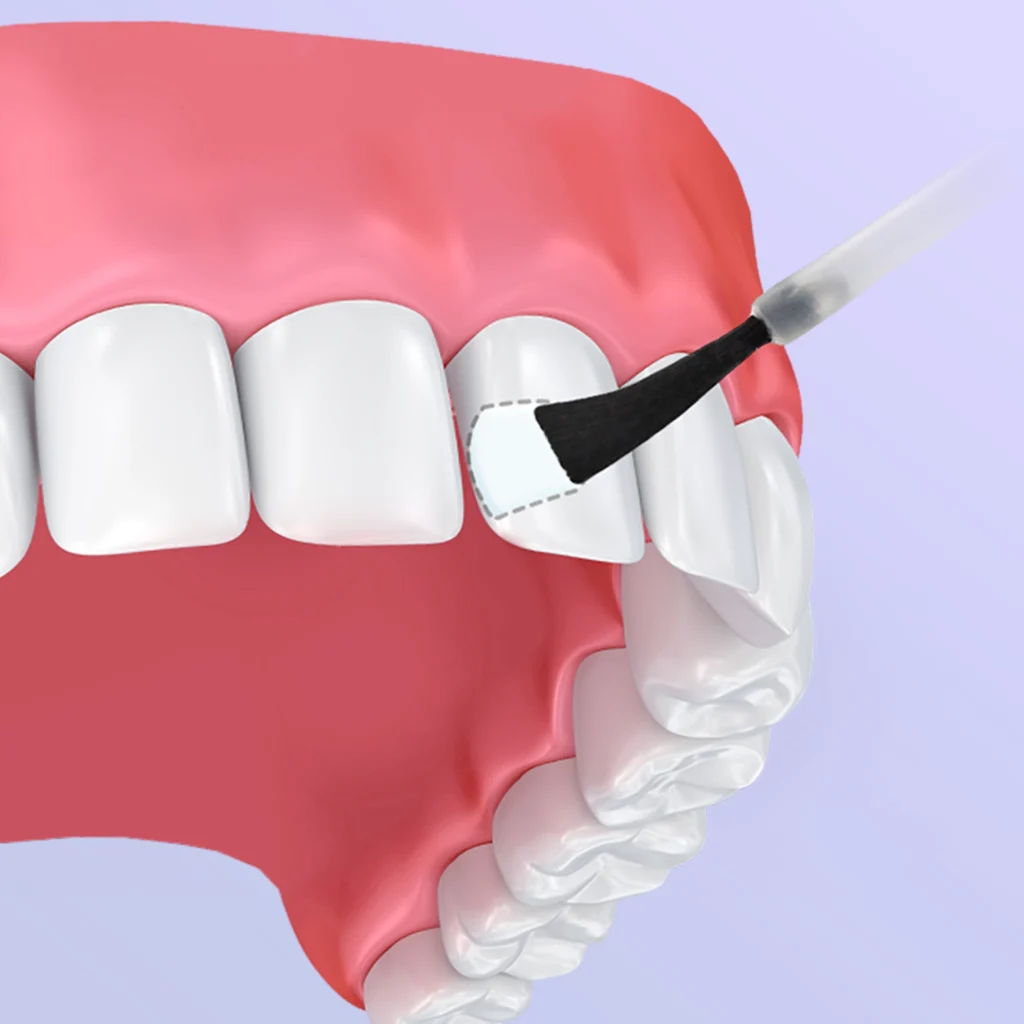

- وارنیش فلوراید: در سنین ۳ تا ۶ ساله، همانند ژل فلوراید می توان بجای دهان شویه فلوراید از وارنیش فلوراید، با مقدار کمتر و غلظت بیشتر استفاده کرد که در مطب ها توسط برس مخصوص و در منزل بر روی مسواک مالیده می شود و تا ۲۴ ساعت نیاز به مسواک زدن نمی باشد.